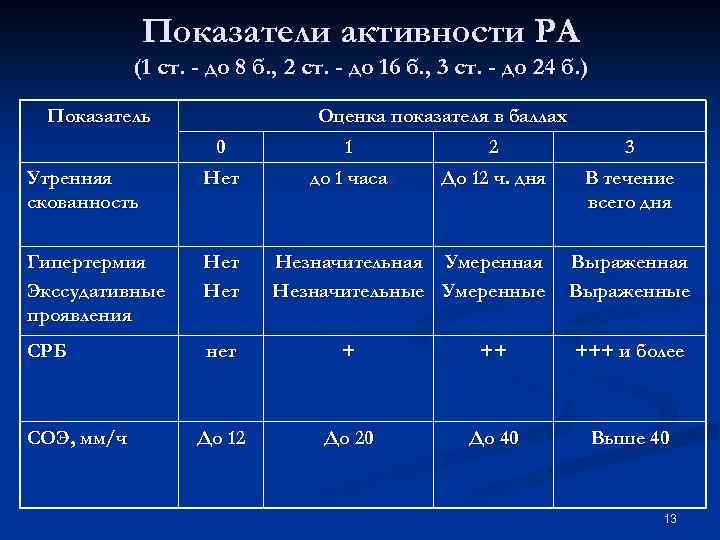

Показатели активности РА (1 ст. - до 8 б. , 2 ст. - до 16 б. , 3 ст. - до 24 б. ) Показатель Оценка показателя в баллах 0 1 2 3 Утренняя скованность Нет до 1 часа До 12 ч. дня В течение всего дня Гипертермия Экссудативные проявления Нет СРБ нет + ++ +++ и более До 12 До 20 До 40 Выше 40 СОЭ, мм/ч Незначительная Умеренная Незначительные Умеренные Выраженная Выраженные 13

Показатели активности РА (1 ст. - до 8 б. , 2 ст. - до 16 б. , 3 ст. - до 24 б. ) Показатель Оценка показателя в баллах 0 1 2 3 Утренняя скованность Нет до 1 часа До 12 ч. дня В течение всего дня Гипертермия Экссудативные проявления Нет СРБ нет + ++ +++ и более До 12 До 20 До 40 Выше 40 СОЭ, мм/ч Незначительная Умеренная Незначительные Умеренные Выраженная Выраженные 13